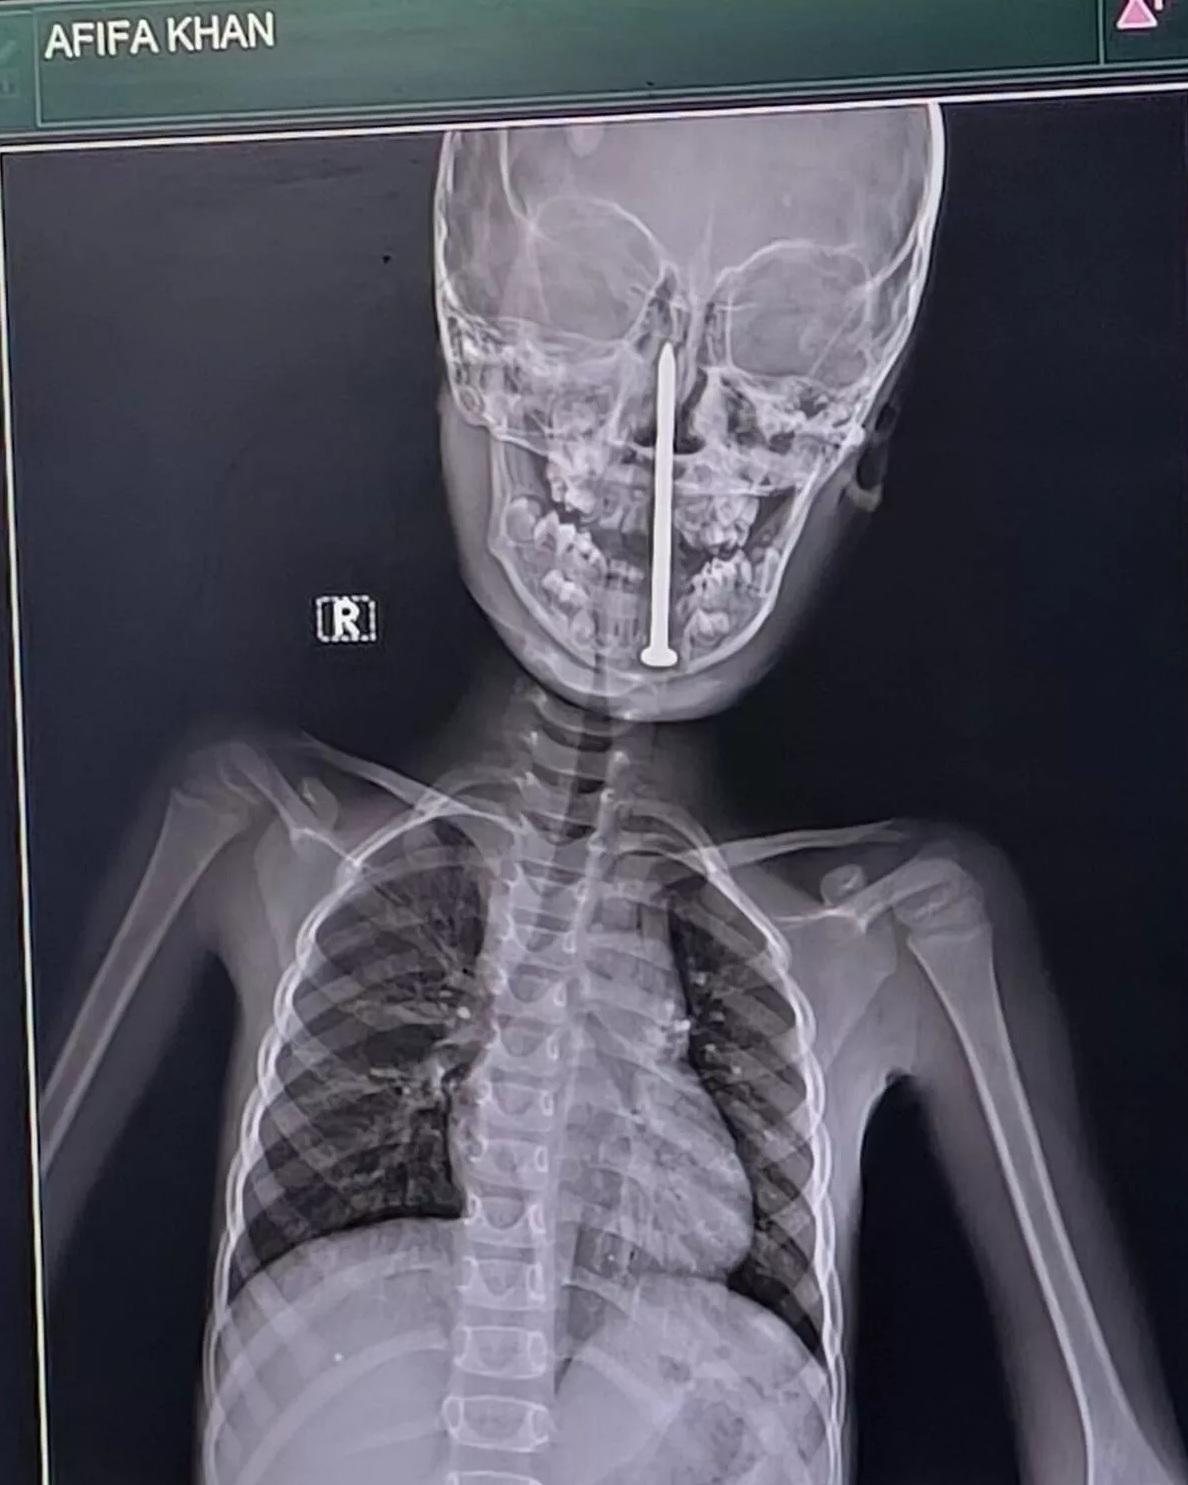

X光檢查顯示,8厘米長鐵釘從下顎進入,直插男童腦部。(互聯網)

北方邦勒克瑙喬治國王醫學大學(King George's Medical University)創傷外科主任蒂瓦里表示,經磁力共振及電腦掃描檢查後發現,當時鐵釘尖端已深入男童的腦部,距離主要血管相當近,情況十分危急。但他也驚嘆,鐵釘剛好能避開腦部這條主要血管,「實在是奇蹟」。

與死神搶人,醫生團隊最終決定進行一次高風險手術,結合顯微手術與神經導航技術,他們小心翼翼地將8厘米長的鐵釘從男童的頭部取出。手術歷時10個小時,過程驚險,在醫護團隊精準操作下完成。